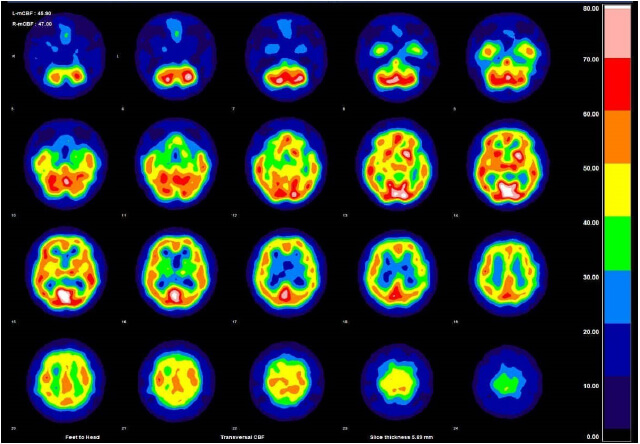

spectの画像

![spect 撮って診る認知症genki55.net|SPECT検査[認知症の進行状況がわかる]](http://genki55.net/img/spect09.gif)